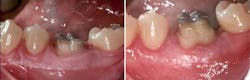

- Improper selection and use of obturation material and techniques. A material such as Thermafil is very technique sensitive and if not used properly would certainly lead to root canal failure. Once obturated, it may appear excellent on the radiograph with the material seemingly filled to the apex, but you could see the presence of a large periapical radiolucency on the radiograph in a failed case, which could indicate potential loss or no seal at the apex.